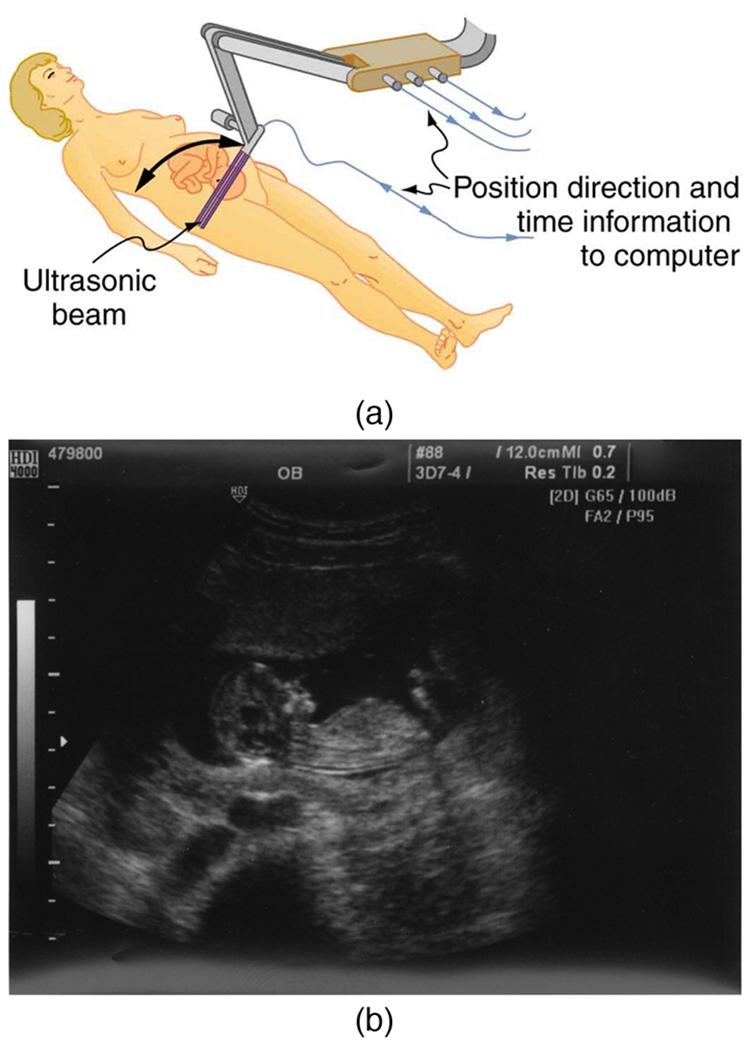

The most common ultrasound applications produce an image like that shown in Figure 17.47. The speaker-microphone broadcasts a directional beam, sweeping the beam across the area of interest. This is accomplished by having multiple ultrasound sources in the probe’s head, which are phased to interfere constructively in a given, adjustable direction. Echoes are measured as a function of position as well as depth. A computer constructs an image that reveals the shape and density of internal structures.

How much detail can ultrasound reveal? The image in Figure 17.47 is typical of low-cost systems, but that in Figure 17.48 shows the remarkable detail possible with more advanced systems, including 3D imaging. Ultrasound today is commonly used in prenatal care. Such imaging can be used to see if the fetus is developing at a normal rate, and help in the determination of serious problems early in the pregnancy. Ultrasound is also in wide use to image the chambers of the heart and the flow of blood within the beating heart, using the Doppler effect (echocardiology).

Whenever a wave is used as a probe, it is very difficult to detect details smaller than its wavelength Indeed, current technology cannot do quite this well. Abdominal scans may use a 7-MHz frequency, and the speed of sound in tissue is about 1540 m/s—so the wavelength limit to detail would be . In practice, 1-mm detail is attainable, which is sufficient for many purposes. Higher-frequency ultrasound would allow greater detail, but it does not penetrate as well as lower frequencies do. The accepted rule of thumb is that you can effectively scan to a depth of about into tissue. For 7 MHz, this penetration limit is , which is 0.11 m. Higher frequencies may be employed in smaller organs, such as the eye, but are not practical for looking deep into the body.